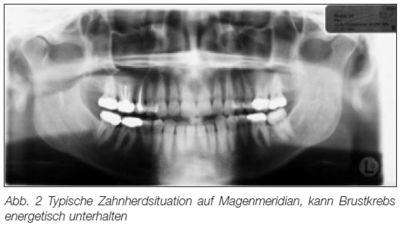

Fig.2: Situation typique d'infections dentaires sur le méridien de l'estomac, [cela] peut entretenir de façon énergétique le cancer du sein.

Illustration tiré d'un article de Thomas Rau chez "Sanum-Post" [3]

D'après des données non publiées de Rau, il aurait constaté que, chez 147 patientes sur 150 atteintes d'un cancer du sein, une ou plusieurs dents se trouvaient sur le méridien de la tumeur.